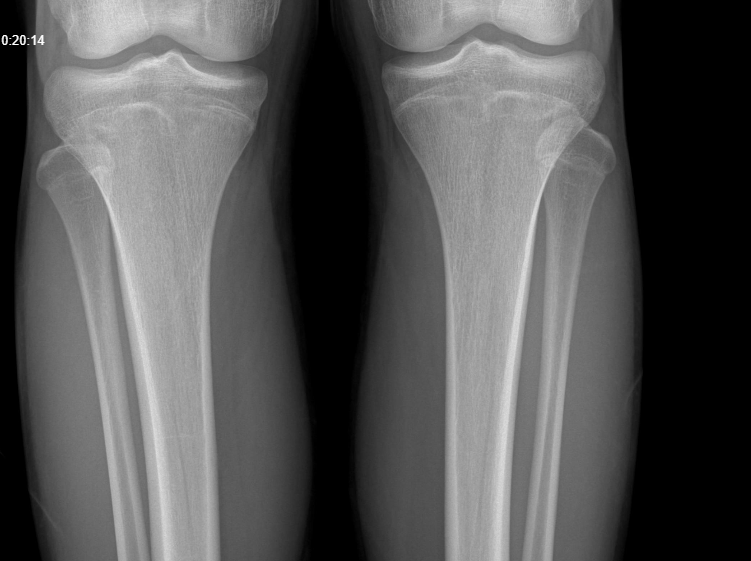

A growth plate (or an Epiphyseal plate) is a region of cartilage near the ends of long bones in children and adolescents where new bone tissue is created, causing the bone to grow in length and width.

This process continues until adolescence, when the growth plates harden into solid bone, a process called "closing" or “fusing”.

Male growth plates tend to fuse at around 16-19, once your plates have fused/closed, they will not grow any longer or wider.

Now, to find out if your growth plates are fused or not, we’re going to look at your wrist & knees for your height, and at your clavicles for your frame.

Above I've added 3 figures, from open ( A ) to fully fused ( C ), those are your growth plates, if theres a visible line like in B, they’re still open, but closer to fusion. ( You will typically see this in X-rays of teenagers). Whereas if you don’t see any lines at all, it means the cartilage has hardened into solid bone, ending any growth potential.

If there’s a visible gap or a full line, your growth plates are open, if there’s no visible line, they’re closed.